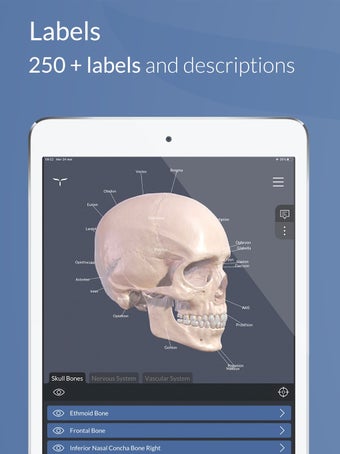

Para ayudar en el aprendizaje y la memorización, la aplicación incluye una vasta colección de textos científicos divididos en tres niveles cognitivos, que van desde una visión general hasta definiciones altamente detalladas.